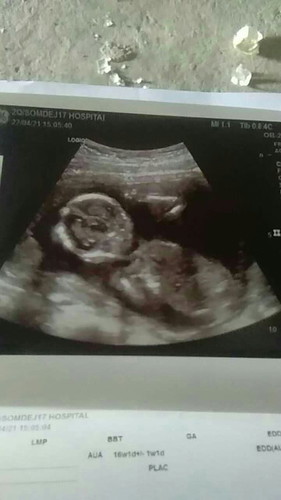

1.เดินเยอะๆลูกจะได้คลอดง่าย 2.ทำงานเยอะๆจะได้คลอดง่าย 3.ใส่กางเกงแบบรัดจะได้ออกง่าย เราก็ทำตามทำคำพูดของคนแก่ได้เดือนหนึ่งพอมาวันหนึ่งเราตื่นนอนแล้วลุกนั่งมีความรู้สึกปวดท้องมากเหมือนปวดท้องประจำเดือน. พอเราลุกขึ้นคือไหลพรวดมา เราก็เลยไปเข้าห้องน้ำ แล้วมีเลือดสดออกจากช่องคลอด ด้วยความที่เราท้องแรกเราก็คิดว่าประจำเดือนมาปกติเลยโทให้พี่สาวซื้อมาให้. พอพี่สาวรู้เรื่องก็รีบพาไปโรงพยาบาล รอประมานชั่งโมงกว่าๆได้เข้าตรวจ หมออัลตร้าซาวด์ให้ คือตอนนั้นจิตใจไม่อยู่กับเนื้อกับตัวคิดว่าลูกจะไม่อยู่กับแล้ว สุดท้ายหมออัลตร้าซาวด์ให้ก็ยังเห็นน้องอยู่ หมอเลยบอกกับเราว่าน้องหัวใจยังเต้นปกติ ตอนนี้เราอยู่ในภาวะแท้งคุกคาม พักผ่อนเยอะๆ พยายามนอน พยายามอย่าเดิน สู้ไปด้วยกันน้ะลูก ลูกจะต้องรอด #ขอบคุณล่วงหน้านะคะ #ใครมีประสบการณ์ #ท้องแรกคะ